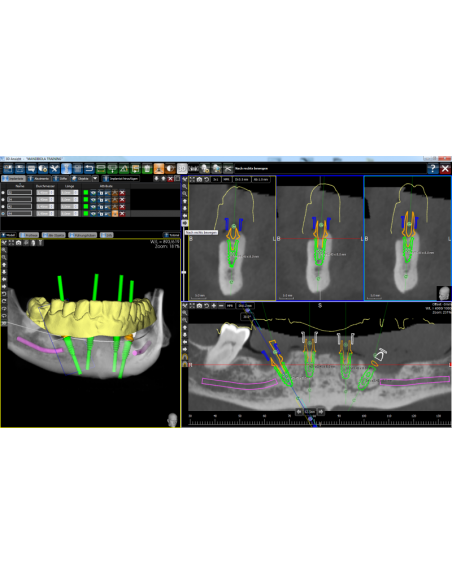

Standardowe wyposażenie kasety chirurgicznej ICX-Magellan

Materiały do pobrania: Protokół chirurgiczny

Szablony i wsparcie techniczne: